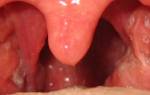

- покраснение горла;

При ларинготрахеите основной очаг воспаления сосредоточен в слизистой горла, затрагивает голосовые связки. Человек на несколько дней теряет возможность разговаривать, ощущает сильное жжение. Першение мешает проглатывать пищу, пить воду. Чтобы облегчить боль, рекомендуется принимать лекарства на основе ибупрофена: Нурофен, Миг 400, Новиган, Ибуклин.